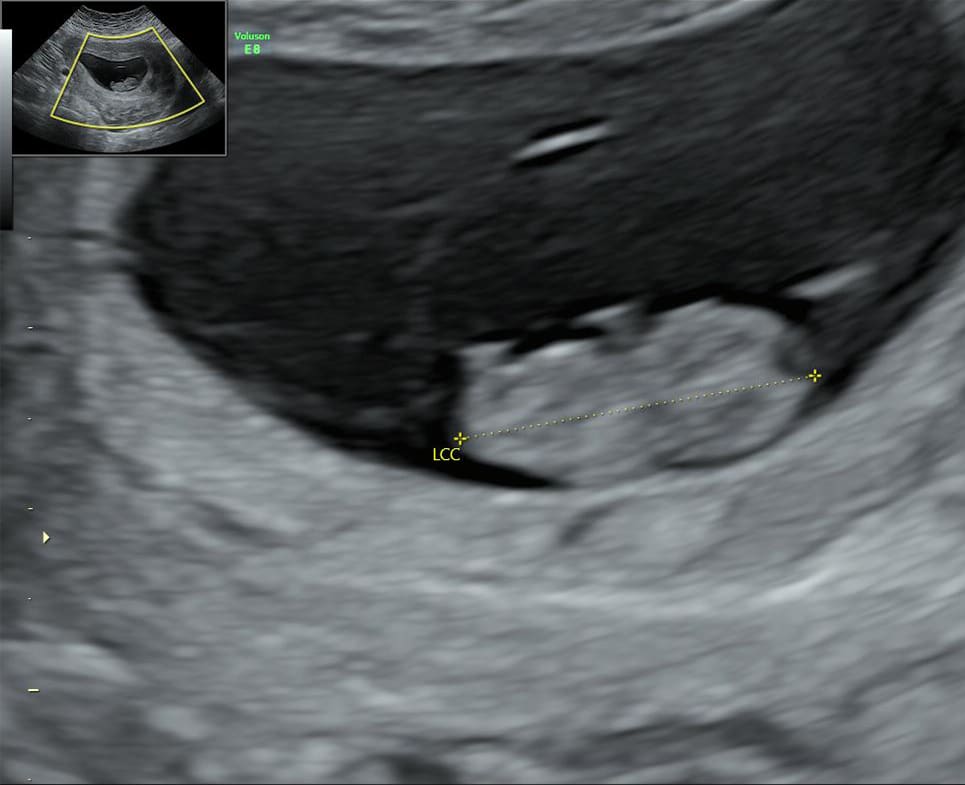

1. L’échographie de datation (7 à 9 SA , soit environ 1 mois 1/2 de grossesse)

C’est souvent la première rencontre avec votre bébé.

Réalisée par voie abdominale ou parfois par voie endovaginale , elle permet :

• De confirmer la grossesse et sa localisation (intra-utérine)

• De vérifier le nombre d’embryons (grossesse simple ou gémellaire)

• De mesurer la longueur de l’embryon pour dater précisément la grossesse

• D’observer l’activité cardiaque

C’est une échographie brève, mais très importante pour poser les bases du suivi de grossesse.